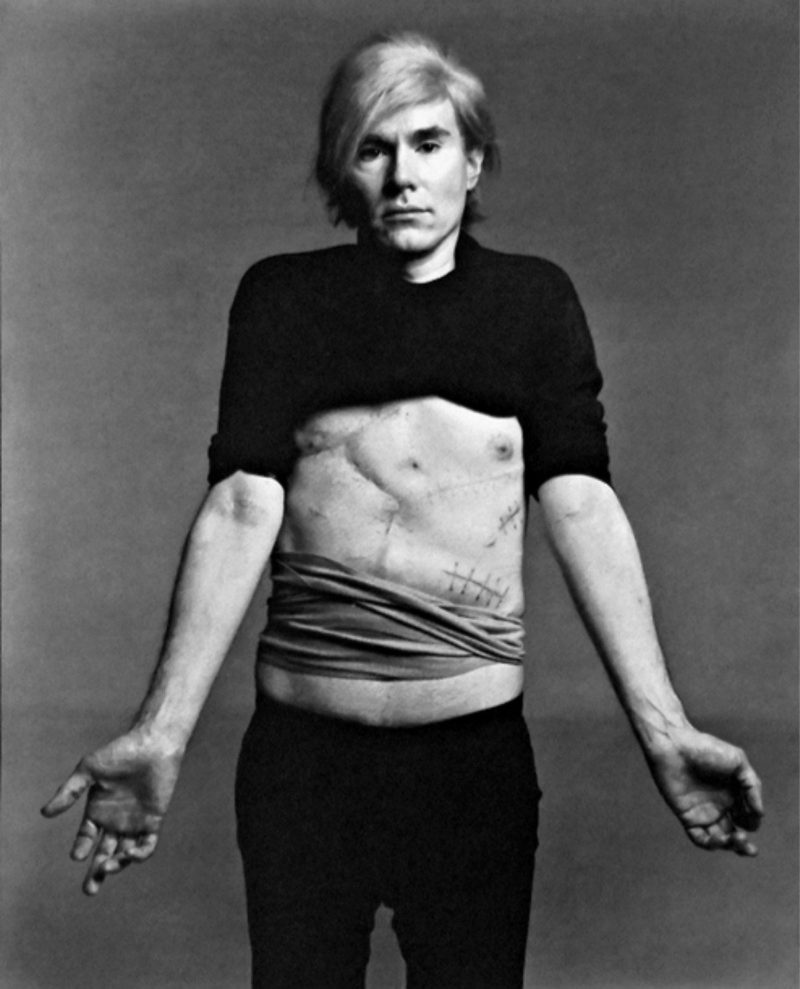

Why did Andy Warhol die? – Public Delivery